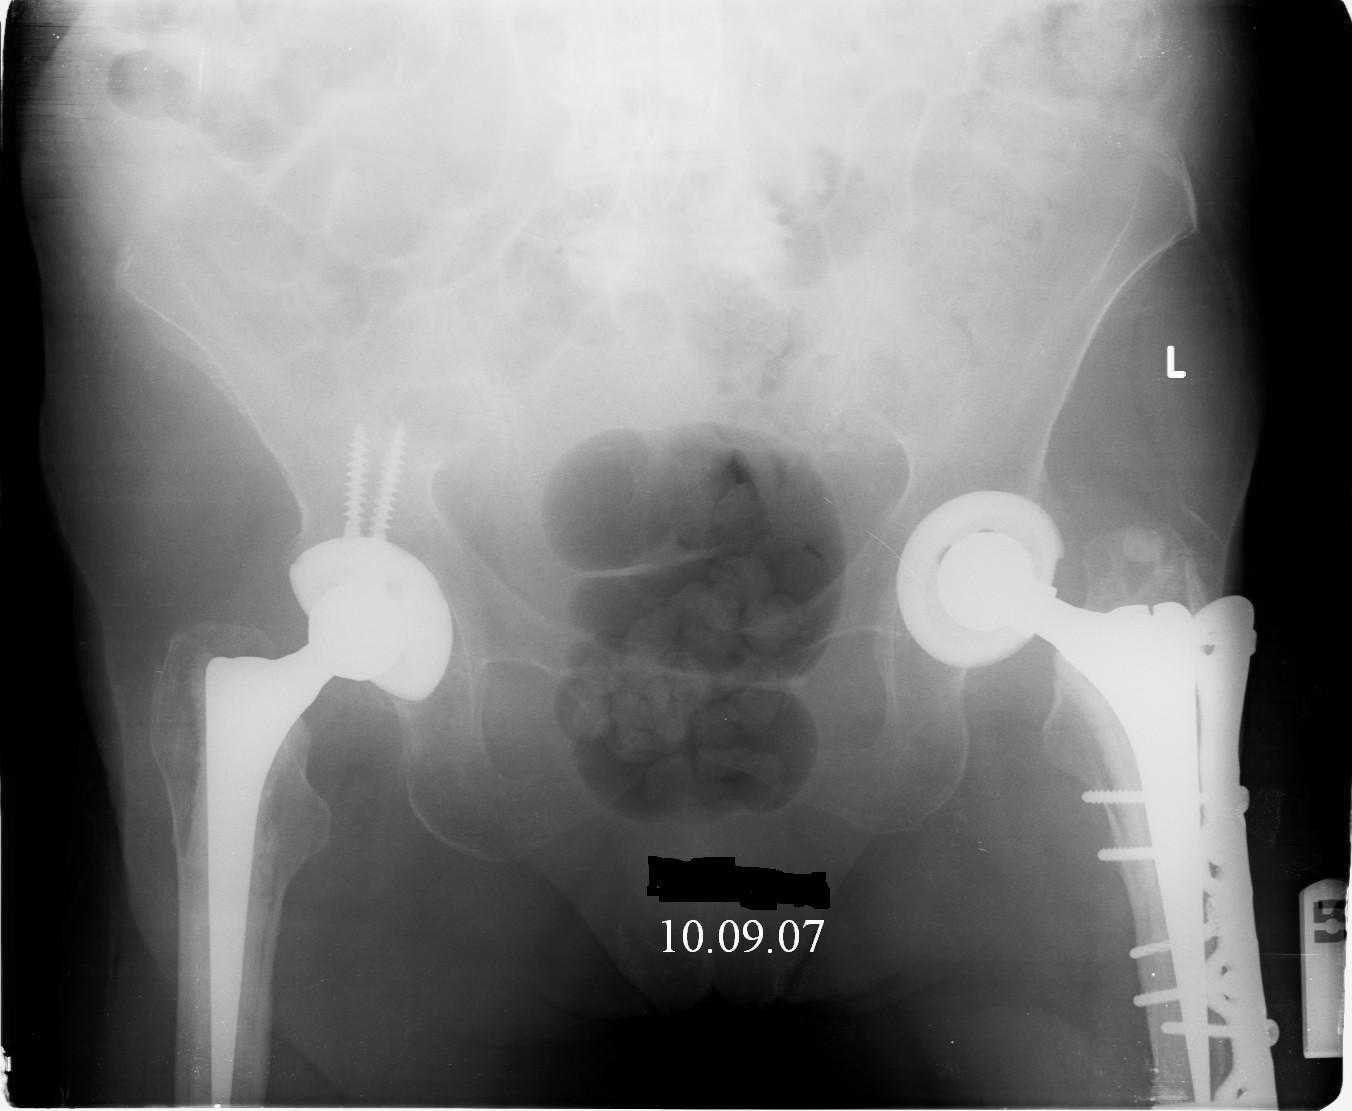

Hello! This is just illustration in one of the choice of treatment